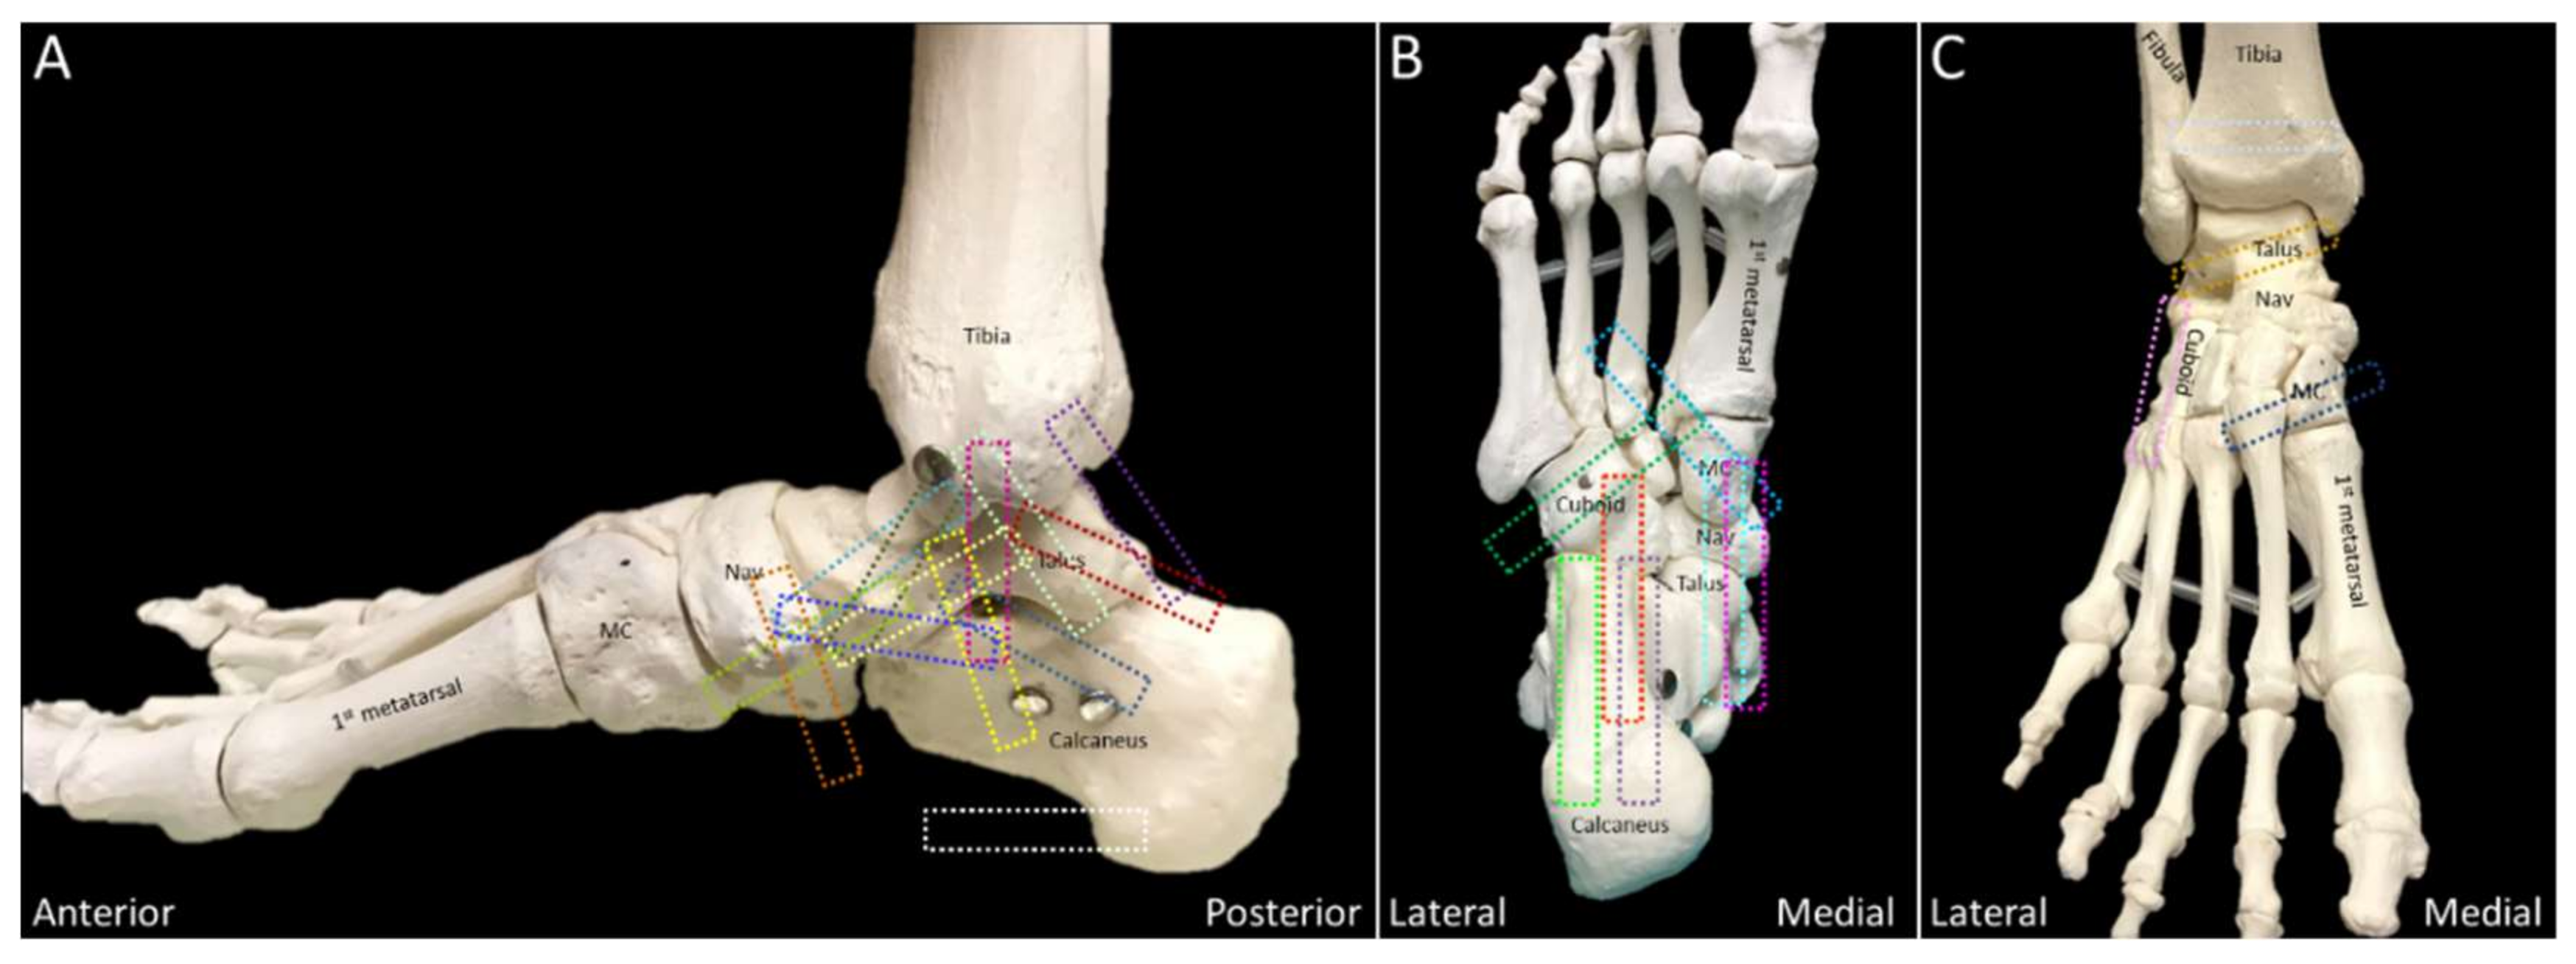

2.7. Deltoid Ligament

2.7.1. Anatomy

2.7.2. Scanning Technique

2.7.3. Clinical Relevance

2.8. Spring Ligament

2.8.1. Anatomy

2.8.2. Scanning Technique

2.8.3. Clinical Relevance

2.10. Lisfranc Ligament Complex

2.10.1. Anatomy

2.10.2. Scanning Technique

2.10.3. Clinical Relevance